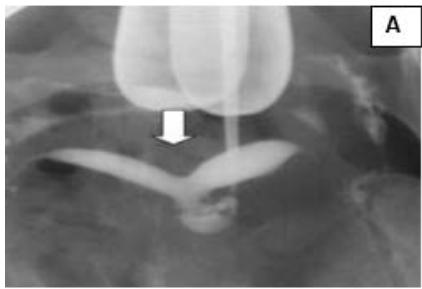

A 33-year-old female, married for 9 years, with previous 2 spontaneous abortions at 4-5 months of gestation, presented with secondary infertility. USG and

HSG revealed bicornuate uterus with approximately equal sized right and left horns. Metroplasty was performed and follow-up USG showed a single uterine cavity. (Fig. 2)

Figure 2: A: HSG s/o Bicornuate uterus. B: Bicornuate uterus on laparotomy. C: Vasopressin injected to minimize the blood loss during surgery. D: Transverse incision taken over uterine fundus. E: Uterine cavity opened. F: Edges approximated & sutured vertically